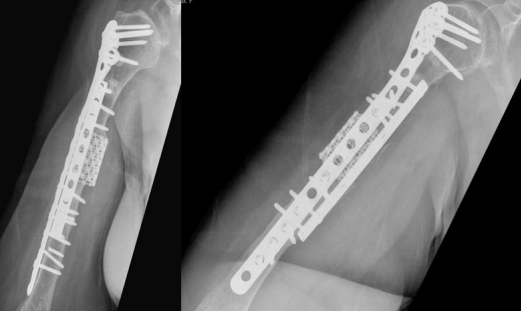

The patient was admitted and taken for her fourth surgery (third revision) on 1 August 2020. The implant and iliac crest bone graft were removed. Fibrous tissue was debrided, and fracture edges were freshened and medullary canals reopened. A 5 cm fibular autograft was harvested and placed in the bone defect, and fixation was performed with a broad 4.5 cm locking compression plate with cemented screws for proximal fixation. Postoperative radiographs are shown in Figure 6.

Figure 06

On serial follow-ups, the patient showed slow healing up to 6 months postoperatively. Follow ups continued for another 6 months but showed no progression of callus. Arrested partial healing was confirmed on CT scans, despite stable fixation, and the patient was symptomatic in the form of pain limiting daily activities. A bone scan was performed to evaluate for infection as the cause of partial healing and showed no evidence of infection. Radiographs at the 1-year follow-up are shown in Figure 7.

Figure 07